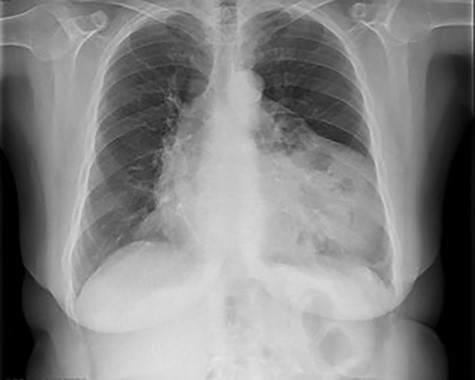

She had a chest X-ray done (Fig. 1) that showed widening of the mediastinum, as well as a few air-fluid levels, which raised suspicion of a diaphragmatic hernia. She also had a thoracic CT done (Fig. 2) that revealed a large hernia in the anterior mediastinum, containing transverse colon and a significant amount of ‘omentum,’ causing right side heart deviation.

Chest X-ray showing widening of the mediastinum and a few air-fluid levels

Once a patient presents a widening of the mediastinum, shifting of heart and mediastinum (usually to the right), or presence of thoracic air-fluid levels on a chest X-ray, one should always consider the possibility of a diaphragmatic hernia, regardless of their age.